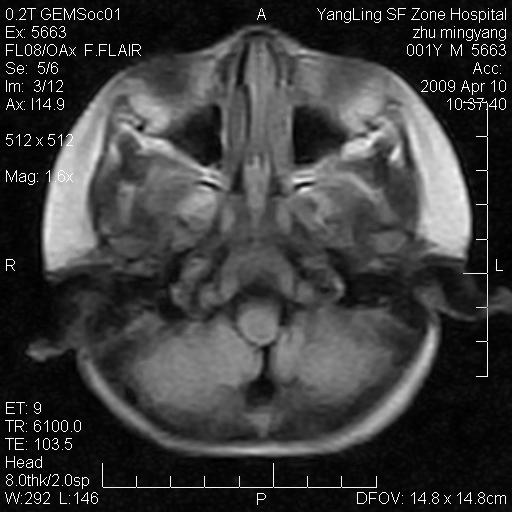

患者:1岁半,两天前外伤收住我院,ct检查小脑占位

考虑星形细胞瘤,建议增强

髓母细胞瘤或血管母细胞瘤,增强后可以鉴别;影像资料见 <。鱼博浪老师的《中枢神经系统ct与mr鉴别诊断》 小脑部肿瘤章节。

髓母细胞瘤或血管母细胞瘤!支持!

支持考虑髓母细胞瘤

考虑----髓母细胞瘤可能性大

考虑髓母细胞瘤或室管膜瘤。

支持髓母细胞瘤。

考虑髓母细胞瘤。

考虑髓母细胞瘤或星形细胞瘤

考虑髓母细胞瘤.

考虑髓母细胞瘤可能性大。

小脑肿瘤.考虑髓母细胞瘤可能.

就病灶部位及临床资料首先考虑髓母.